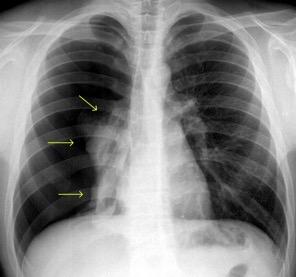

BRONCOGRAMA

“Forma” del broncograma

“Normal” “Rígido”

Neumonía…....60,87%

Tuberculosis. 32,56%

Ca. de pulmón. 25,64%

Ca. de pulmón. 64,10%%

Neumonía…....41,86%

Tuberculosis. 39,13%

“Tortuoso”

“Normal”

Neumonía…....60,8%

Tuberculosis. 25,5%

Ca. de pulmón. 7,69%

“Lumen” del broncograma

“Estenosis”

Ca. de pulmón. 82,05%%

Neumonía…....21,74%

Tuberculosis. 25,58%

Ca. de pulmón. 10,26%

Neumonía….....0%

“Expansión”

Tuberculosis. 20,93% Tuberculosis. 44,19%

Neumonía….....13,04%

Ca. de pulmón. 7,69%%

Qu H et al. The value of the air bronchogram sign on CT image in the identification of different solitary pulmonary consolidation lesions. Medicine 2017